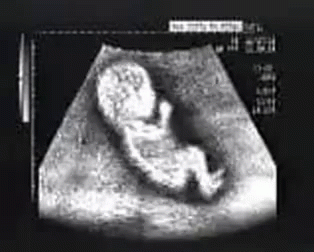

– Hoàn tất siêu âm hình thái: Nếu chưa làm ở tuần 18-19, mẹ nên thực hiện siêu âm tuần 20 để kiểm tra tim, não, cột sống, và các cơ quan bé. Xem kết quả với bác sĩ để đảm bảo bé khỏe mạnh.

– Siêu âm cho thấy bé cử động đều đặn (đá, xoay, nấc cụt), ngón tay/chân hoàn thiện, và lông mi/mày rõ nét. Thật tuyệt vời!